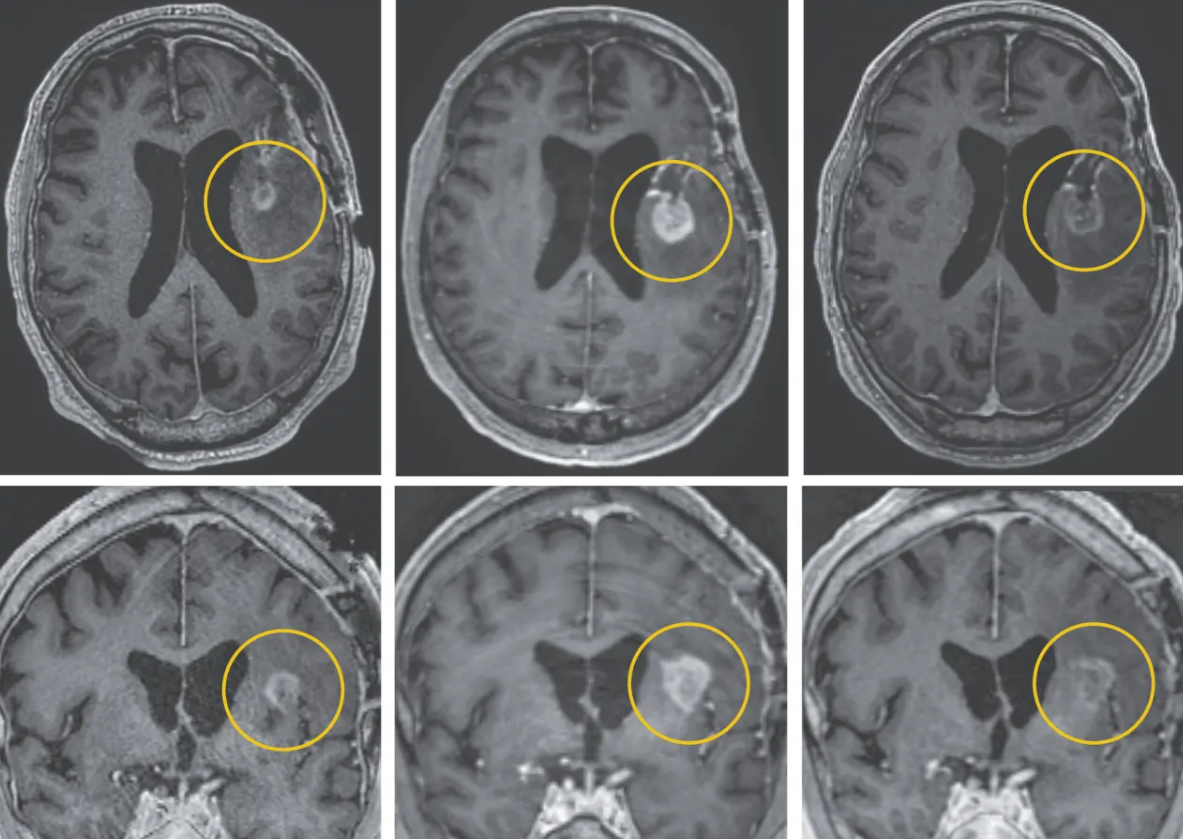

Lo sorprendente es que con una sola dosis administrada directamente en el cerebro, se lograron reducciones significativas del tumor en los primeros pacientes. La resonancia magnética evidenció regresión casi total en uno de ellos, mostrando cómo un nuevo tratamiento contra el cáncer ayudó a mujer de forma tangible. Esta rapidez marca un cambio en la manera de enfrentar el glioblastoma desde el sistema inmunológico.